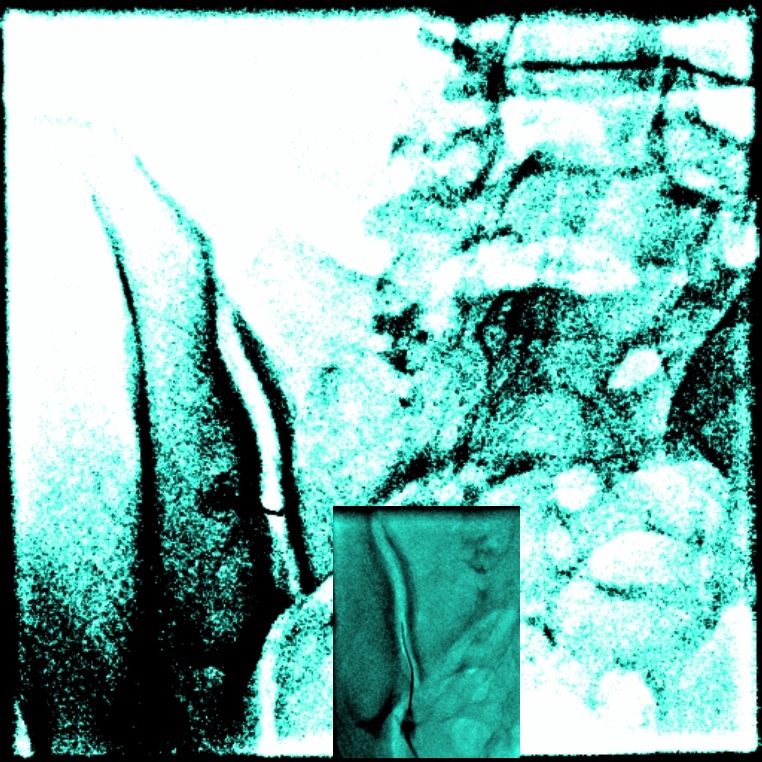

Imagine de ansamblu a articulației sacroiliace stangi. În dreapta-sus, ultimele vertebre lombare care se continuă cu osul sacru iar în stânga se vede articulația sacroiliacă și un ac in poziție la polul inferior. În casetă, un detaliu, acul a pătruns în articulație.

Imagini care ilustrează injectarea sub control radiologic cu substanță de contrast a articulației sacroiliace vazută din lateral.